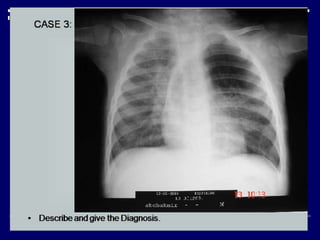

 X-ray chest PA view of adult male (01)

 Opaque left hemi thorax (01)

 Mediastinal shift toward left (01)

 No air-bronchogram, cavitations or bony lesion (02)

 Normal right lung (01)

 Diagnosis: -

Collapse left lung (due to hilar mass ?) (03)

 Advised: -

CECT chest (01)

Findings  X-ray chestPA view of adult male (01)  Opaque left hemi thorax (01)  Mediastinal shift toward left (01)  No air-bronchogram, cavitations or bony lesion (02)  Normal right lung (01)  Diagnosis: - Collapse left lung (due to hilar mass ?) (03)  Advised: - CECT chest (01)